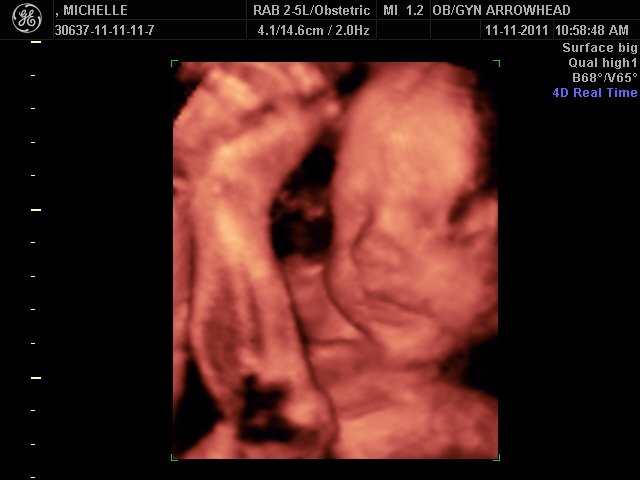

We offer complimentary 3D/4D Ultrasounds to all our OB patients around 30 weeks! The following photos are some examples of our work, shown with permission from our patients.